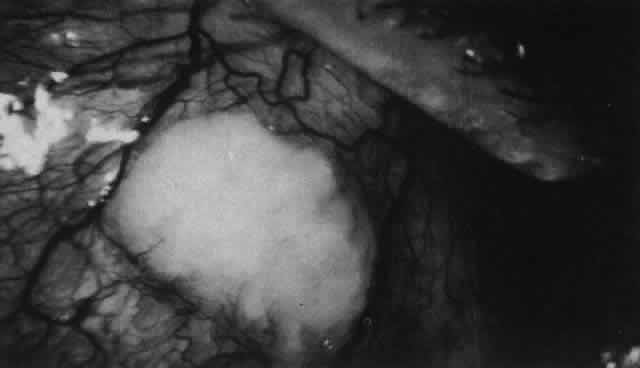

The characteristic features of necrotizing scleritis on fluorescein angiography are hypoperfusion and, eventually, nonperfusion of the vascular networks (Figs. 40 through 43).26 The initial changes are on the venous side of the capillary network; the transit time of the dye increases even if the eye is red and congested. If the disease process persists or has been present for a long time, thrombosis and permanent vaso-occlusive changes occur. These vessels (or the occluded capillary network) are bypassed by the opening of anastomotic channels. New vessels in a granuloma give rise to deep intrascleral leakage of dye (see Fig. 43). Conjunctival and episcleral involvement by the destructive change is late but is always preceded by vaso-occlusive changes that can sometimes be detected with use of the red-free light on the slit lamp (Figs. 44 and 45).

Fig. 40. Early necrotizing scleritis. There is characteristic yellow discoloration of the sclera underlying the conjunctiva at a point of necrosis. In this instance a small filament of tissue has penetrated the conjunctiva.

Fig. 41. Late stage of fluorescein angiogram adjacent to the site of necrosis in the same patient as in Figure 40. Although the eye is uniformly congested, the area near the necrosis shows vascular shutdown, whereas the rest of the conjunctiva and episclera is normally perfused.

Fig. 42. Late arterial phase of fluorescein angiogram in a patient with necrotizing scleritis. All the vessels except the main trunk and the vessels around the limbal perforating vessels are occluded and remain unperfused throughout the angiogram.

Fig. 43. Late venous phase of angiogram of a patient with necrotizing scleritis showing late deep leakage from vessels on the surface of the sclera and leakage of the capillary network at the limbus and the vessels draining it, together with poor or absent perfusion of the remaining vessels.